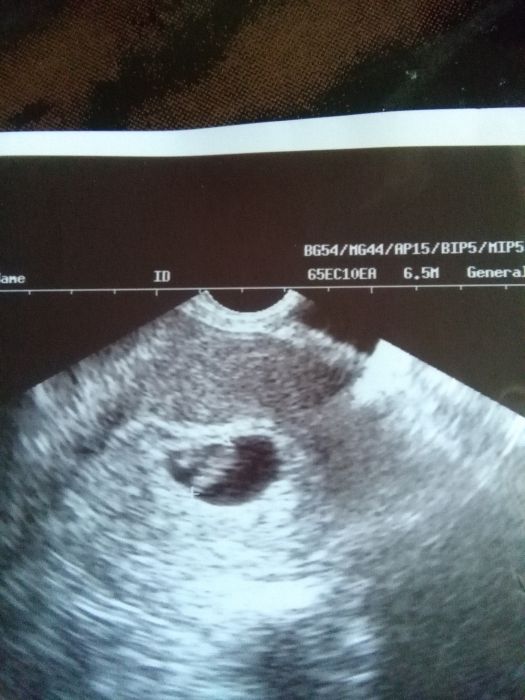

[934970]Tak jsem byla u dr. ráno, a prý je dost malé, odpovídá spíše opravdu 5tt, ale mohla jsem mít posunutou ovulaci, viděla jsem jen černoukuličku..prý vajíčko tam je, ale nic jiného nevidí. Počkáme týden, špiním pořád, mám brát utrogestan a klidový režim, kontola ve středu za týden a uvidíme, jestli malé je opravdu malé a povyroste a špinění je jen z uhnizďování hlouběji či cévky, nebo se nevyvíjí jak má a tak mi to tělo dává najevo.....tak musím čekat a ležet.